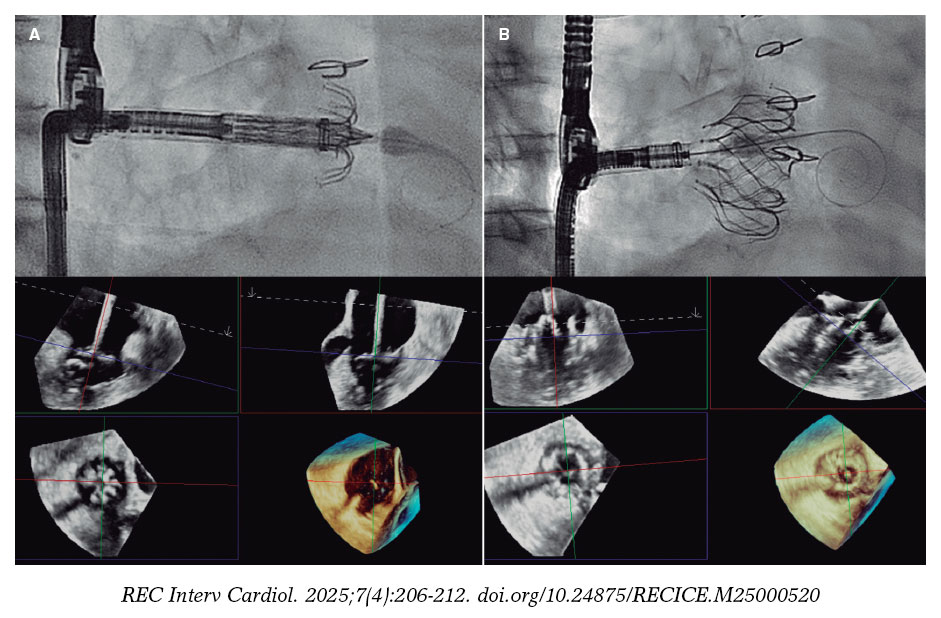

When a CN is suspected on coronary angiography, intracoronary imaging—preferably OCT, with IVUS as an alternative—will be performed to confirm the diagnosis. After confirmation of a CN in the target lesion, patients will be randomized on a 1:1 ratio to receive a DEB or a DES. Randomization will be stratified to ensure a balanced distribution of eruptive and non-eruptive nodules across both treatment groups. A CN (figure 2) will be defined as a calcified segment with an accumulation of protruding nodular calcification (small calcium deposits) with disruption of the fibrous cap (eruptive CN) or an intact thick fibrous cap (non-eruptive CN).28-30

Figure 2. Calcified nodule appearance on angiography (A), optical coherence tomography (eruptive [B] and non-eruptive [C]) and intravascular ultrasound (D).